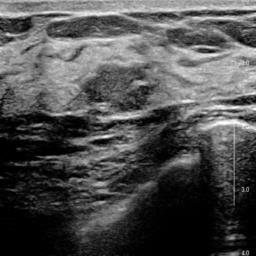

Ultrasonography is an important routine examination for breast cancer diagnosis, due to its non-invasive, radiation-free and low-cost properties. However, it is still not the first-line screening test for breast cancer due to its inherent limitations. It would be a tremendous success if we can precisely diagnose breast cancer by breast ultrasound images (BUS). Many learning-based computer-aided diagnostic methods have been proposed to achieve breast cancer diagnosis/lesion classification. However, most of them require a pre-define ROI and then classify the lesion inside the ROI. Conventional classification backbones, such as VGG16 and ResNet50, can achieve promising classification results with no ROI requirement. But these models lack interpretability, thus restricting their use in clinical practice. In this study, we propose a novel ROI-free model for breast cancer diagnosis in ultrasound images with interpretable feature representations. We leverage the anatomical prior knowledge that malignant and benign tumors have different spatial relationships between different tissue layers, and propose a HoVer-Transformer to formulate this prior knowledge. The proposed HoVer-Trans block extracts the inter- and intra-layer spatial information horizontally and vertically. We conduct and release an open dataset GDPH&GYFYY for breast cancer diagnosis in BUS. The proposed model is evaluated in three datasets by comparing with four CNN-based models and two vision transformer models via a five-fold cross validation. It achieves state-of-the-art classification performance with the best model interpretability.